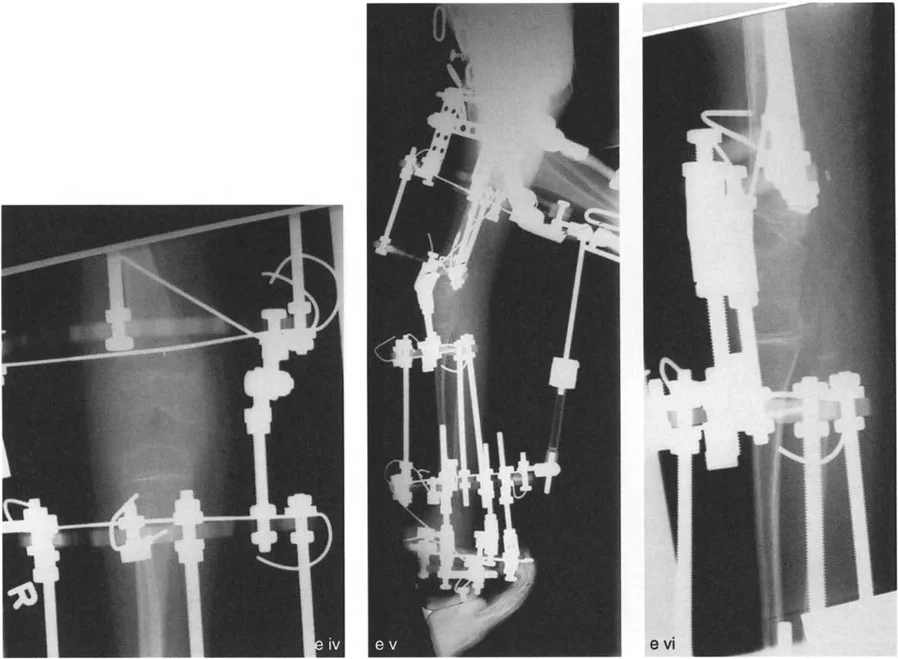

- الأشعة الجانبية الطويلة للطرف السفلي بالكامل أثناء الوقوف في أقصى بسط (Standing Long-Leg Lateral View in Maximum Extension): تُستخدم لتقييم تحدد حركة الركبة (FFD) والركبة الارتدادية (Recurvatum)، وتحديد ما إذا كان التشوه عظميًا أو ناتجًا عن تقلص في الأنسجة الرخوة.

- قد يُستخدم في حالات معينة للحصول على صور ثلاثية الأبعاد للعظام، خاصة في التخطيط لجراحات تصحيح التشوهات المعقدة أو لتقييم دوران العظام.

- التصحيح التدريجي: في حالات تحدد الحركة الشديدة أو المعقدة، قد يكون التصحيح التدريجي باستخدام التثبيت الخارجي هو الخيار الأكثر أمانًا.